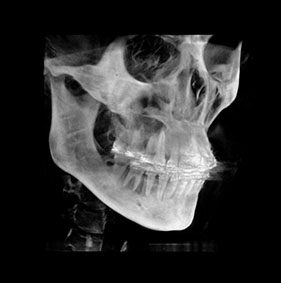

3D CT분석을 통한

정확한 코 재수술

원인 분석

코 재수술은 문제의 원인을

정확한 파악하는 것이 중요합니다.

V브이성형외과의

코성형 전담 의료진은

환자와 면밀한 상담을 통해서

현재 불만족의 원인을 파악하고

개선을 위한 방법을 모색합니다.

3D CT 분석을 통해서 해부학적인 상태를 확인하고,

기존 코수술로 인한 문제를 파악할 수 있습니다.